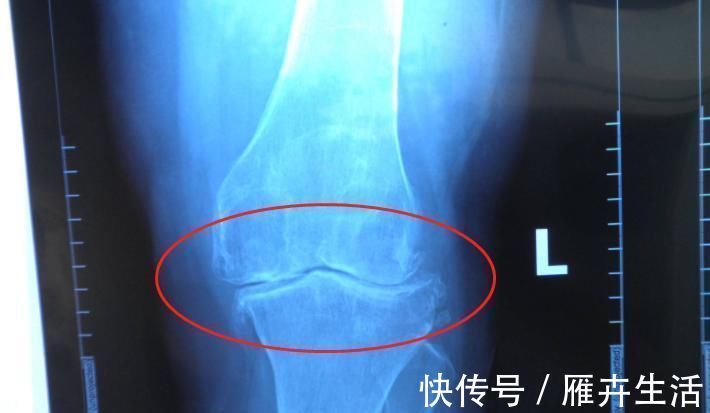

4、骨骺线闭合情况

简单说,骨骺线就是骨与骨之间的一条软组织,当这条软骨没有骨化之前,大家都有继续长高的机会,当骨骺线闭合后,身体停止长高。

同理,男生的身高也受骨骺线闭合情况影响,有研究证明,男生在25岁之前都有继续长高的可能性,但前提是,骨骺线没有闭合,抓住长高的最后一丝希望,或许身高还能再窜一窜。